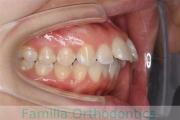

No.22V-498

- 上顎前突

- 側方偏位

- 26歳

- 女性

- 上:

- 44

- 下:

- 8|58

- FEA

- 90万円

上の前歯が出ているのと下の前歯のでこぼこを治したいということで来院されました。左右のズレがあるので、上顎を左右から、下顎は左下のみ小臼歯を抜歯して、アンカースクリューを併用したマルチブラケット法にて治療を行いました。2年強、25回程度の通院が必要でした。

前歯の移動量が多いケースとなりますので、歯根吸収や歯肉退縮のリスクが高めです。